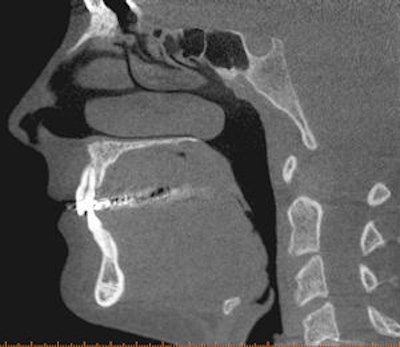

![]() |

| Cone-beam CT images from two different patients. The top CT image was taken to evaluate the mandible for implant purposes; the other was taken to evaluate the maxilla for implant purposes. The images show how much more of the head was exposed than needed to be. Also, one CT was done at 0.25 voxels, which is more resolution than is needed for a typical implant CT. Images courtesy of Dr. Bernard Friedland. |